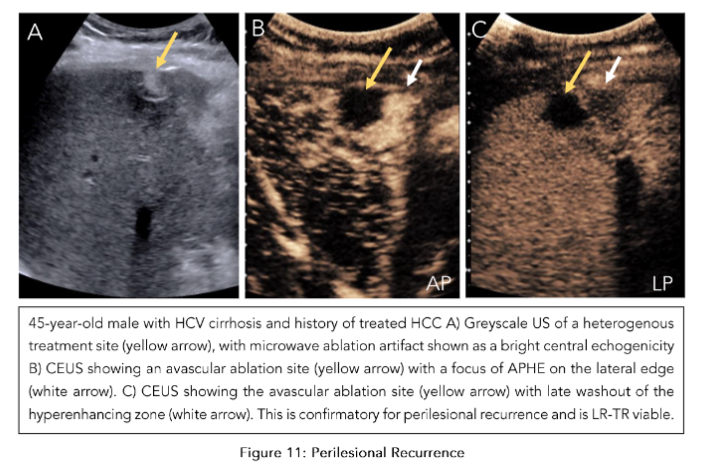

The observations in the secondary surveillance period follow the CEUS LI-RADS treatment response algorithm (TRA)(52). In a technically adequate exam, the ablation site is assessed for both intralesional and perilesional tumor viability. For intralesional viability, if there is no enhancement within the ablation bed, it indicates the absence of a viable tumor. Uncertain viability is characterized by arterial phase hyperenhancement (with or without washout), while hyperenhancement or isoenhancement (with or without washout) suggests the presence of a viable tumor (Figure 10). For perilesional viability, absent viability is characterized by homogeneous enhancement of the ablation margins compared to the rest of the liver. Uncertain viability is characterized by arterial phase hyperenhancement without washout, isoenhancement with washout, or hypoenhancement. The presence of a viable tumor is confirmed by hyperenhancement with washout (Figure 11). Once both these categories are assessed, an overall treatment response score is determined based on their respective contributions. If there is any intralesional or perilesional viability, the overall treatment response score is LI-TR viable. If there is any uncertainty in one without viability present in the other, the overall treatment response score is LR-TR equivocal. Here, an alternative imaging modality like MRI would be useful in clarifying the viability. Only when there is absent viability in both intralesional and perilesional viability is the final category designated as LR-TR nonviable (Figure 12).

Figure 11: Perilesional Recurrence